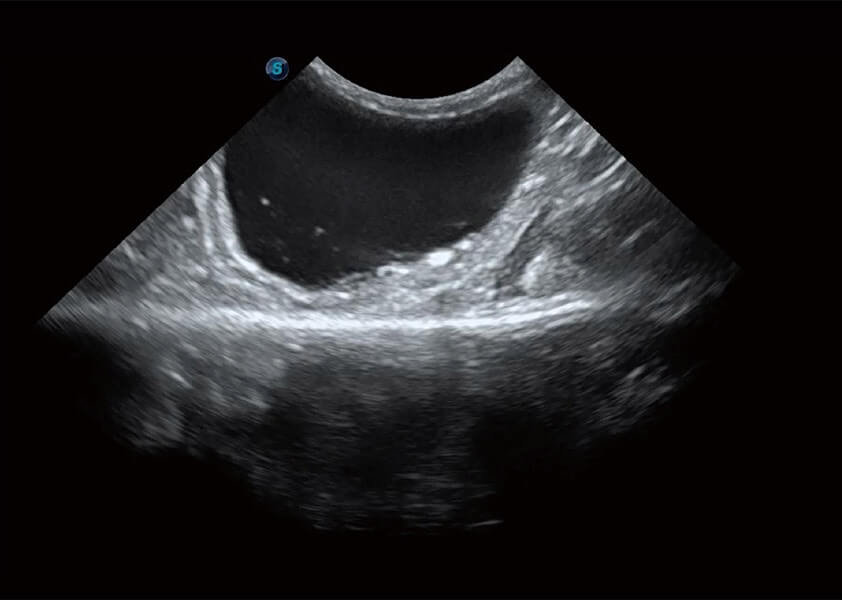

ProPet 60 作为一款高端台式动物超声设备,为动物医生的日常诊断提供了一系列贴合动物临床需求、解决临床实际问题的高级成像功能。凭借全系列高清探头,满足医生对腹部、心脏、生殖、浅表、肌骨等成像的所有需求,切实帮助您提升检查效率,提高诊断信心。

动物是人类最亲密的朋友和最值得信赖的伙伴。乐玩lewin国际也一直致力于探索动物专用的超声影像解决方案。 全新推出的ProPet系列,是乐玩lewin国际在动物超声影像智能化、专业化、精准化的一次跨越式革新。动物不能用言语来表述自己的不适,通过超声影像,ProPet系列搭建了动物医生与不同物种沟通的“桥梁”,为动物医生注入了“治愈之力”。